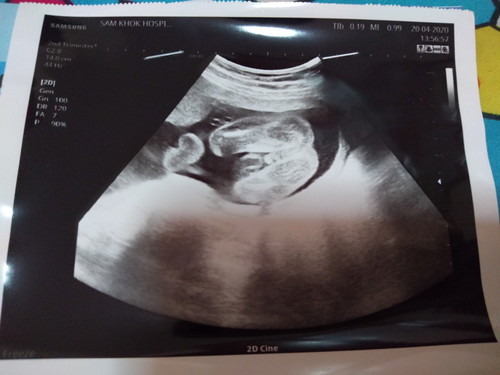

ท้องได้ 22 สัปดาห์แล้วคะ

แม่ๆคิดว่าเพศอะไรคะ

ผู้ชายค่ะ ภาพซาวด์เหมือนกันเลย

ดูไม่เป็นค่ะ แต่คิดว่าเป็น ชาย

ชายค่ะ ป๋องแป๋งชัดขนาดนั้น ☺️

ชายค่ะ ไข่เป็นพวงเลย

ผู้ชายค่ะ ชัดมาก